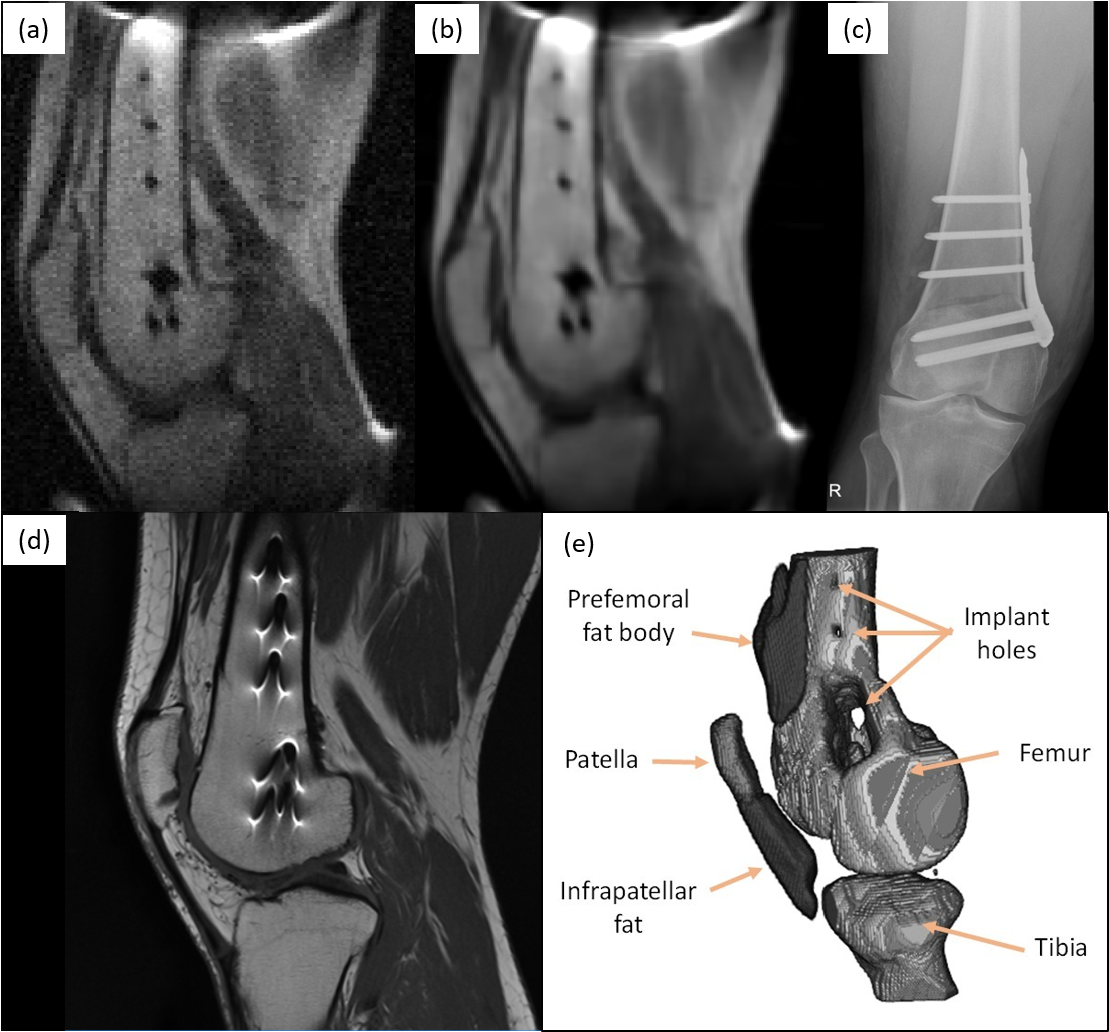

Figure 3: Images of fixation metallic implant attached to the femur, consisting of a plate and seven screws: (a) sagittal view of a raw low-field image acquired with the 70 mT system (single slice from T1subscript𝑇1T_{1}-weighted 3D-TSE acquisition with in-plane resolution of 1.3×21.321.3\times 2 mm2, 12 min scan time, eight years after femoral shaft osteotomy); (b) same, but BM4D-filtered and rescaled by ×2absent2\times 2; (c) lateral X-ray computed radiography (two weeks after surgery); (d) sagittal view of the same knee, acquired with a Siemens Skyra 3 T system (T1subscript𝑇1T_{1}-weighted 2D-TSE acquisition with slice thickness 3.9 mm and pixel resolution 0.26×0.260.260.260.26\times 0.26 mm2, one year after surgery); and (e) 3D reconstruction from T1subscript𝑇1T_{1}-weighted 3D-TSE acquisition with isotropic resolution of 2 mm, 20 min scan time, where selected muscle and fat segments have been removed (eight years after surgery).

In a second set of experiments, we demonstrate in vivo MR images in the presence of metallic implants without the strong susceptibility-induced artifacts typical of high-field acquisitions14, 16, which often hamper post-operative assessment of orthopedic procedures15. The volunteer for these tests had been diagnosed with lateral gonarthrosis due to cartilage damage in their right knee and had a femoral shaft osteotomy to remove pressure from the damaged tissue. The fixation metallic implant screwed to the femur is cleanly visible in a lateral X-ray computed radiographic image (Fig. 3(c)), but leads to high intensity fringes around the metallic hardware in high-field MR images due to incorrect spin mapping (see Fig. 3(d), taken at 3 T). These effects depend supralinearly on the magnetic field strength and are barely perceptible38 at fields <0.1absent0.1<0.1 T. The field dependence is notorious in the images: the SNR and resolution are much higher in the 3 T system, but the metallic implant geometry is accurately defined in our 70 mT 2D and 3D reconstructions, and can be readily segmented with standard data post-processing. The low-field images were taken in 12 min (Fig. 3(a) and (b)) and 20 min (Fig. 3(e)) with T1subscript𝑇1T_{1}-weighted 3D-TSE acquisitions (Methods).

The knee images in Fig. 3(a) and (b) were acquired with a T1subscript𝑇1T_{1}-weighted 3D-TSE sequence, with FoV=200×200×180FoV200200180\text{FoV}=200\times 200\times 180 mm3, a pixel resolution of 1.3×2×91.3291.3\times 2\times 9 mm3, ETL=5ETL5\text{ETL}=5, TE=20TE20\text{TE}=20 ms, TR=200TR200\text{TR}=200 ms, BW=37.5BW37.5\text{BW}=37.5 kHz, and 9 averages for a total scan time of 12 min.

The knee image in Fig. 3(e) was acquired with a T1subscript𝑇1T_{1}-weighted 3D-TSE sequence, with FoV=200×200×180FoV200200180\text{FoV}=200\times 200\times 180 mm3, a pixel resolution of 2×2×22222\times 2\times 2 mm3, ETL=10ETL10\text{ETL}=10, TE=20TE20\text{TE}=20 ms, TR=300TR300\text{TR}=300 ms, BW=22.5BW22.5\text{BW}=22.5 kHz, and 4 averages for a total scan time of 20 min.